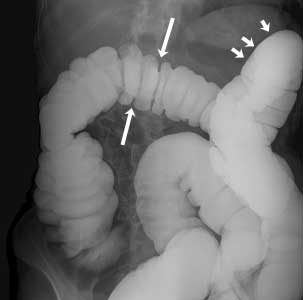

Normal Barium Enema

Normal colon

This image shows a normal colon filled with barium. The barium shows up as white on the image. The arrows point to the normal curves of the colon.